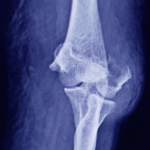

El área de trauma ortopédico se especializa en la atención de pacientes que han sufrido fracturas, luxaciones o lesiones complejas derivadas de caídas, accidentes laborales, deportivos o de tránsito. Nuestro equipo interdisciplinario aplica protocolos de atención inmediata para reducir riesgos y complicaciones, ofreciendo desde tratamientos conservadores hasta procedimientos quirúrgicos avanzados. Además, acompañamos el proceso de recuperación con terapias orientadas a recuperar la movilidad y prevenir secuelas.

No. Muchas fracturas pueden tratarse de manera conservadora mediante inmovilización y control médico. La cirugía se recomienda cuando los huesos están desplazados, hay compromiso articular, lesiones múltiples o riesgo de mala consolidación. El médico evaluará el tratamiento más seguro y funcional según cada caso.